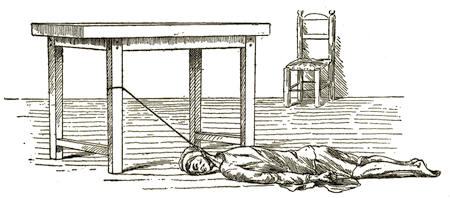

| Medico-Legal Consideration of Death by Mechanical Suffocation. D. S. Lamb, | 705 |